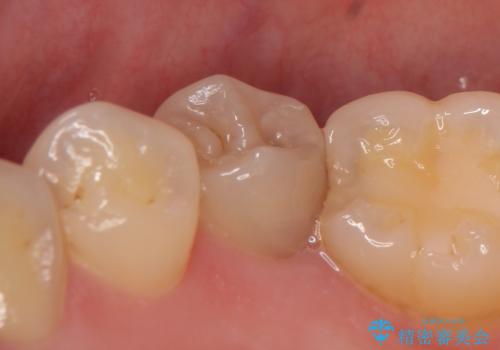

- 右下の奥歯がズキズキ痛むので診て欲しいといらっしゃった方の症例です。

右下5は虫歯が大きく神経は保存不可能だったため、根管治療を行った後、オールセラミッククラウンによる補綴を行いました。